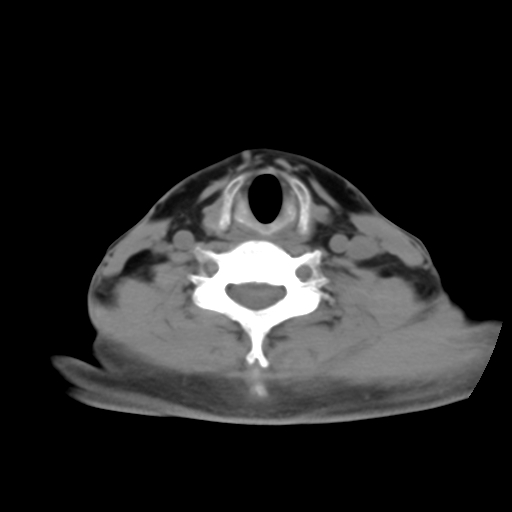

标题: CT24019:男,45岁,发现颈部肿物5个月。 [打印本页]

男,45岁,发现颈部肿物5个月,彩超示:双侧颈部及下颌部软组织增厚。

考虑双侧颈项部良性对称性脂肪增多症。